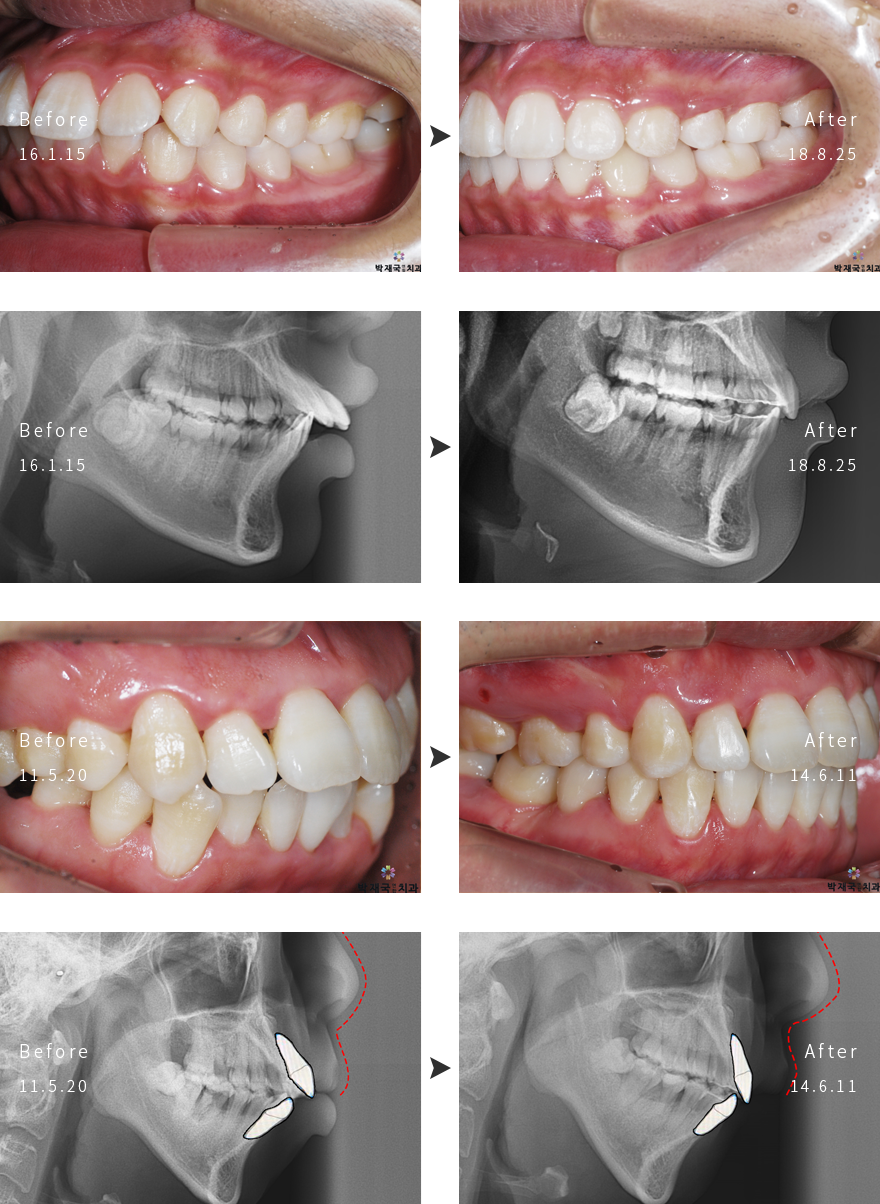

µ¹ÃâÀÔ±³Á¤ »ç·Ê

orthodontic Clinic